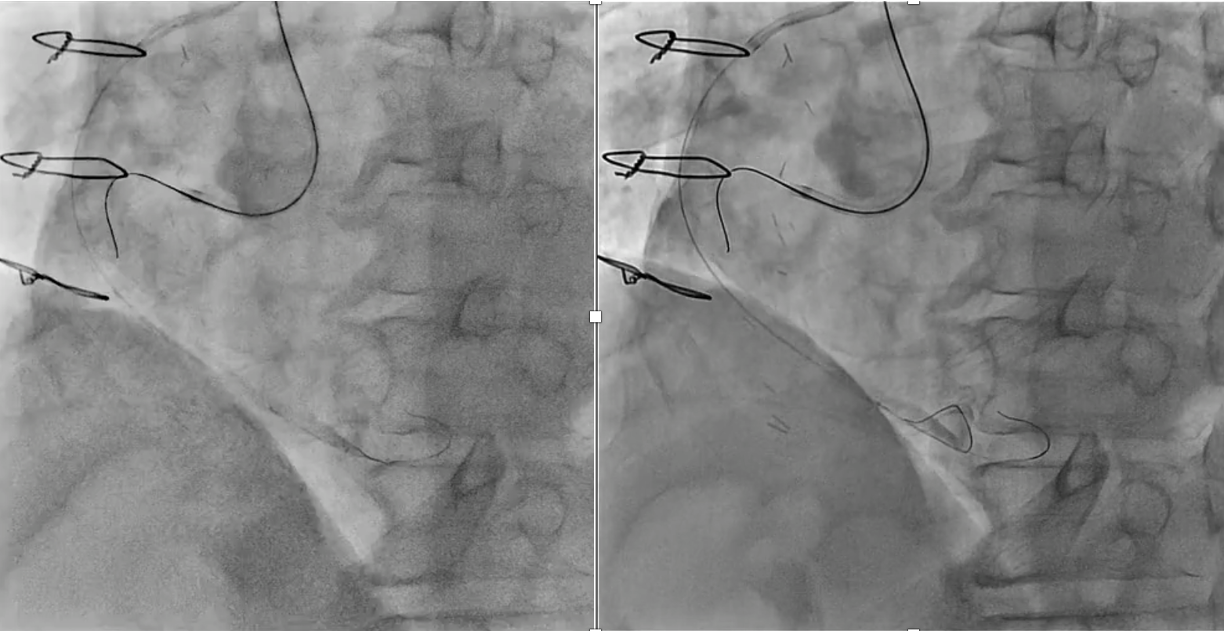

PCI for the degenerated SVG was determined to be at high risk of distal embolism so we planned to perform PCI for native RCA. Antegrade wire crossing was thought to be difficult (J-CTO score was 3 : calcification, bending and lesion length), therefore we planned retrograde approach via SVG. To avoid ischemia during the retrograde procedure, we dilated the severe stenotic lesion in SVG with small balloon and then micro catheter was advanced. It was very difficult to pass the graft anastomosis, but reverse wire technique at distal RCA was effective. Even after the advancement of both antegrade and retrograde wires, it was also difficult to pass the CTO lesion due to strong bending. Finally, retrograde wire was passed with Reverse CART technique and externalization was achieved. After DES implantation, native RCA was nicely revascularized.